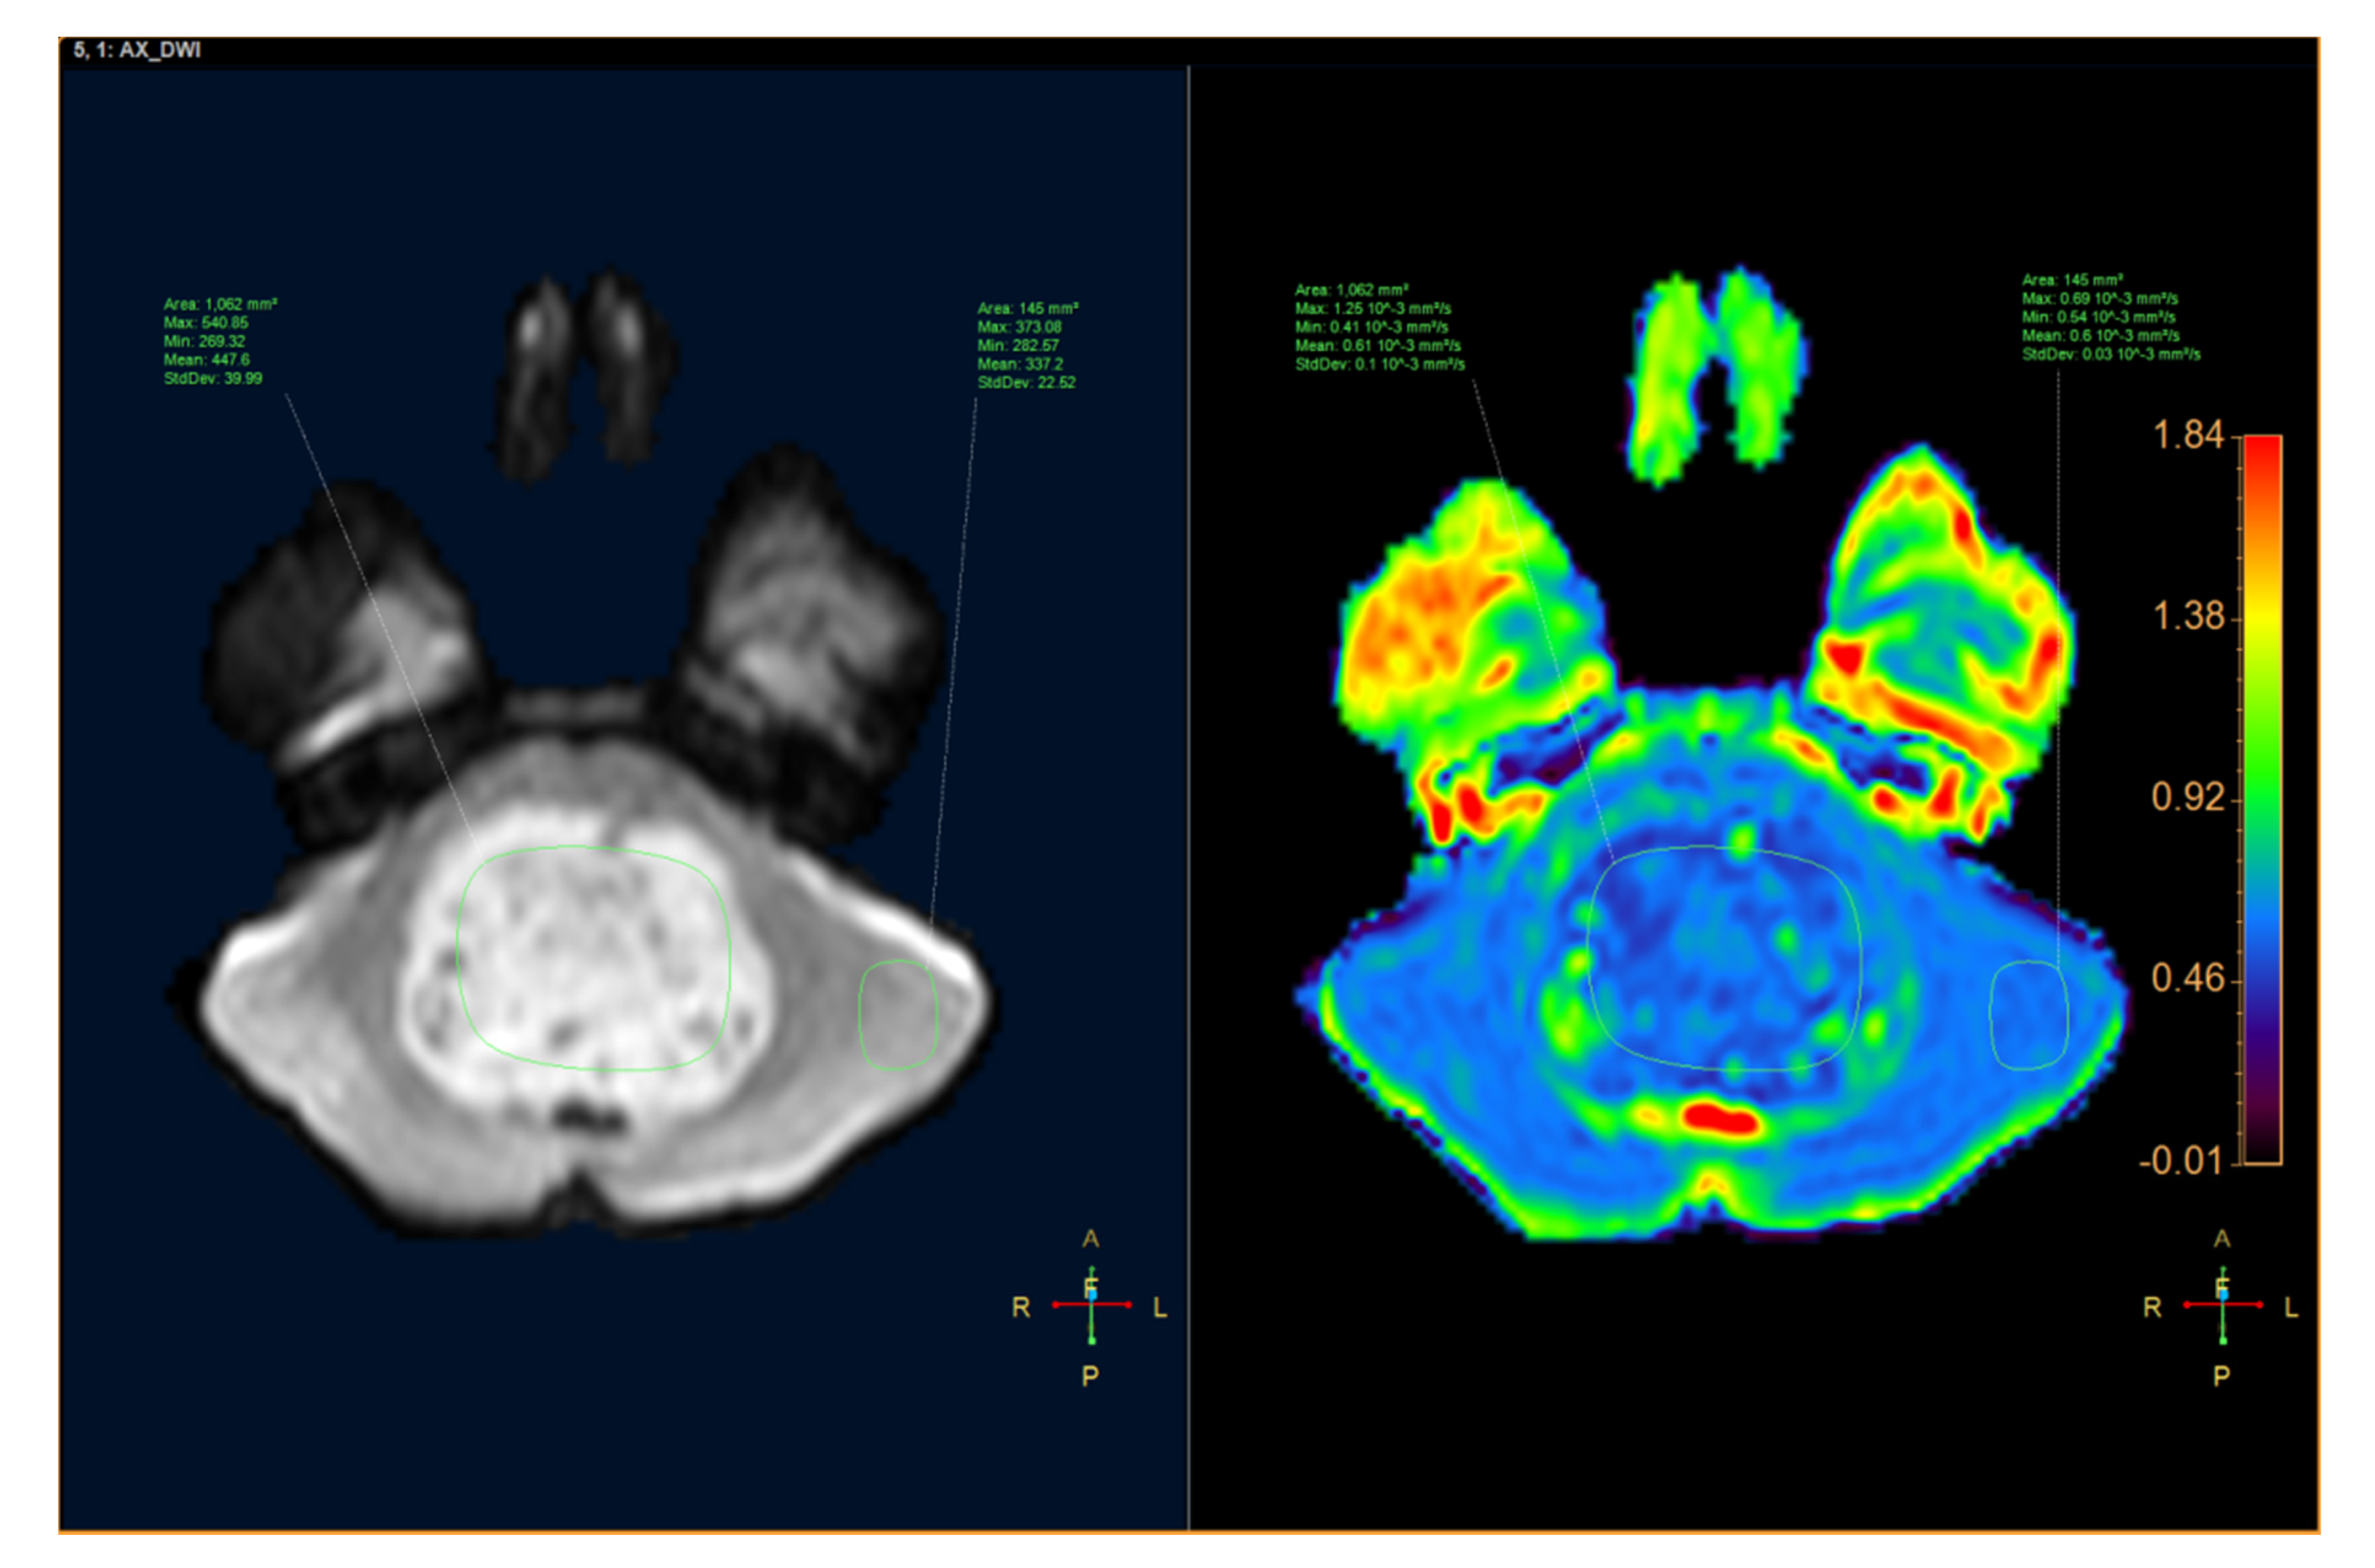

| ADCmax (10−3 mm2/s) | 1.06 (0.58) | 1.64 (0.45) | 0.003 § |

| ADCmin (10−3 mm2/s) | 0.43 (0.11) | 1.11 (0.34) | <0.001 § |

| ADCmean (10−3 mm2/s) | 0.62 (0.19) | 1.39 (0.33) | <0.001 § |

| ADCsd | 0.11 (0.06) | 0.10 (0.05) | 0.967 |